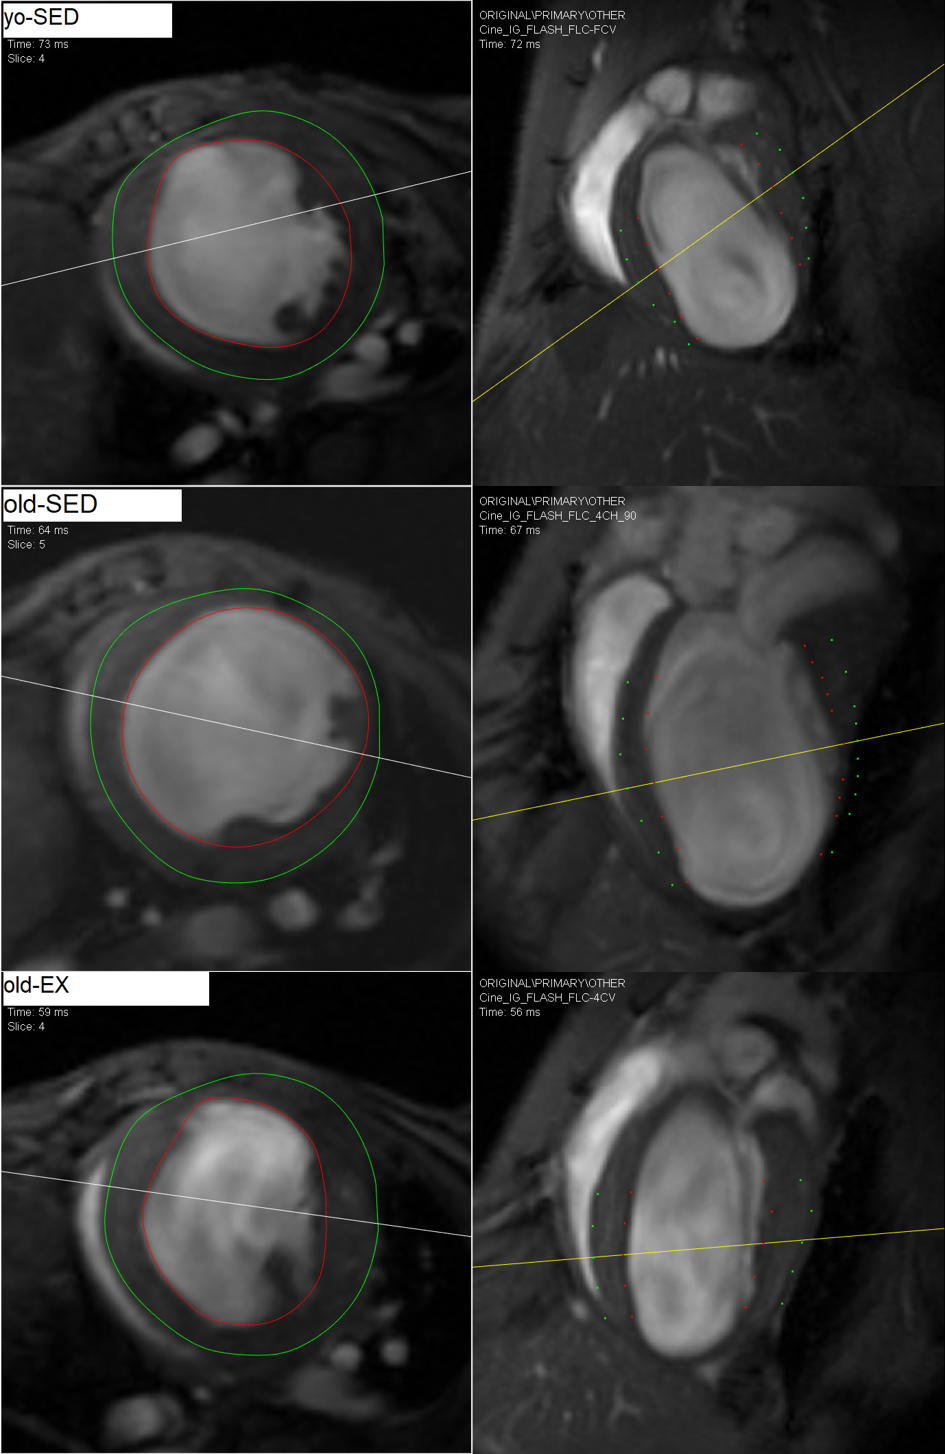

Abb.1: Enddiastolische Kurz- und Längsachsen. Quelle: Autor/Segment (http://segment.heiberg.se).

Die enddiastolische Wanddicke des linken Ventrikels war sowohl im Infarkt-Areal als auch im gesunden Vergleichsareal bei der old-EX-Gruppe signifikant größer als in den Gruppen yo-SED und old-SED (Abb. 2).